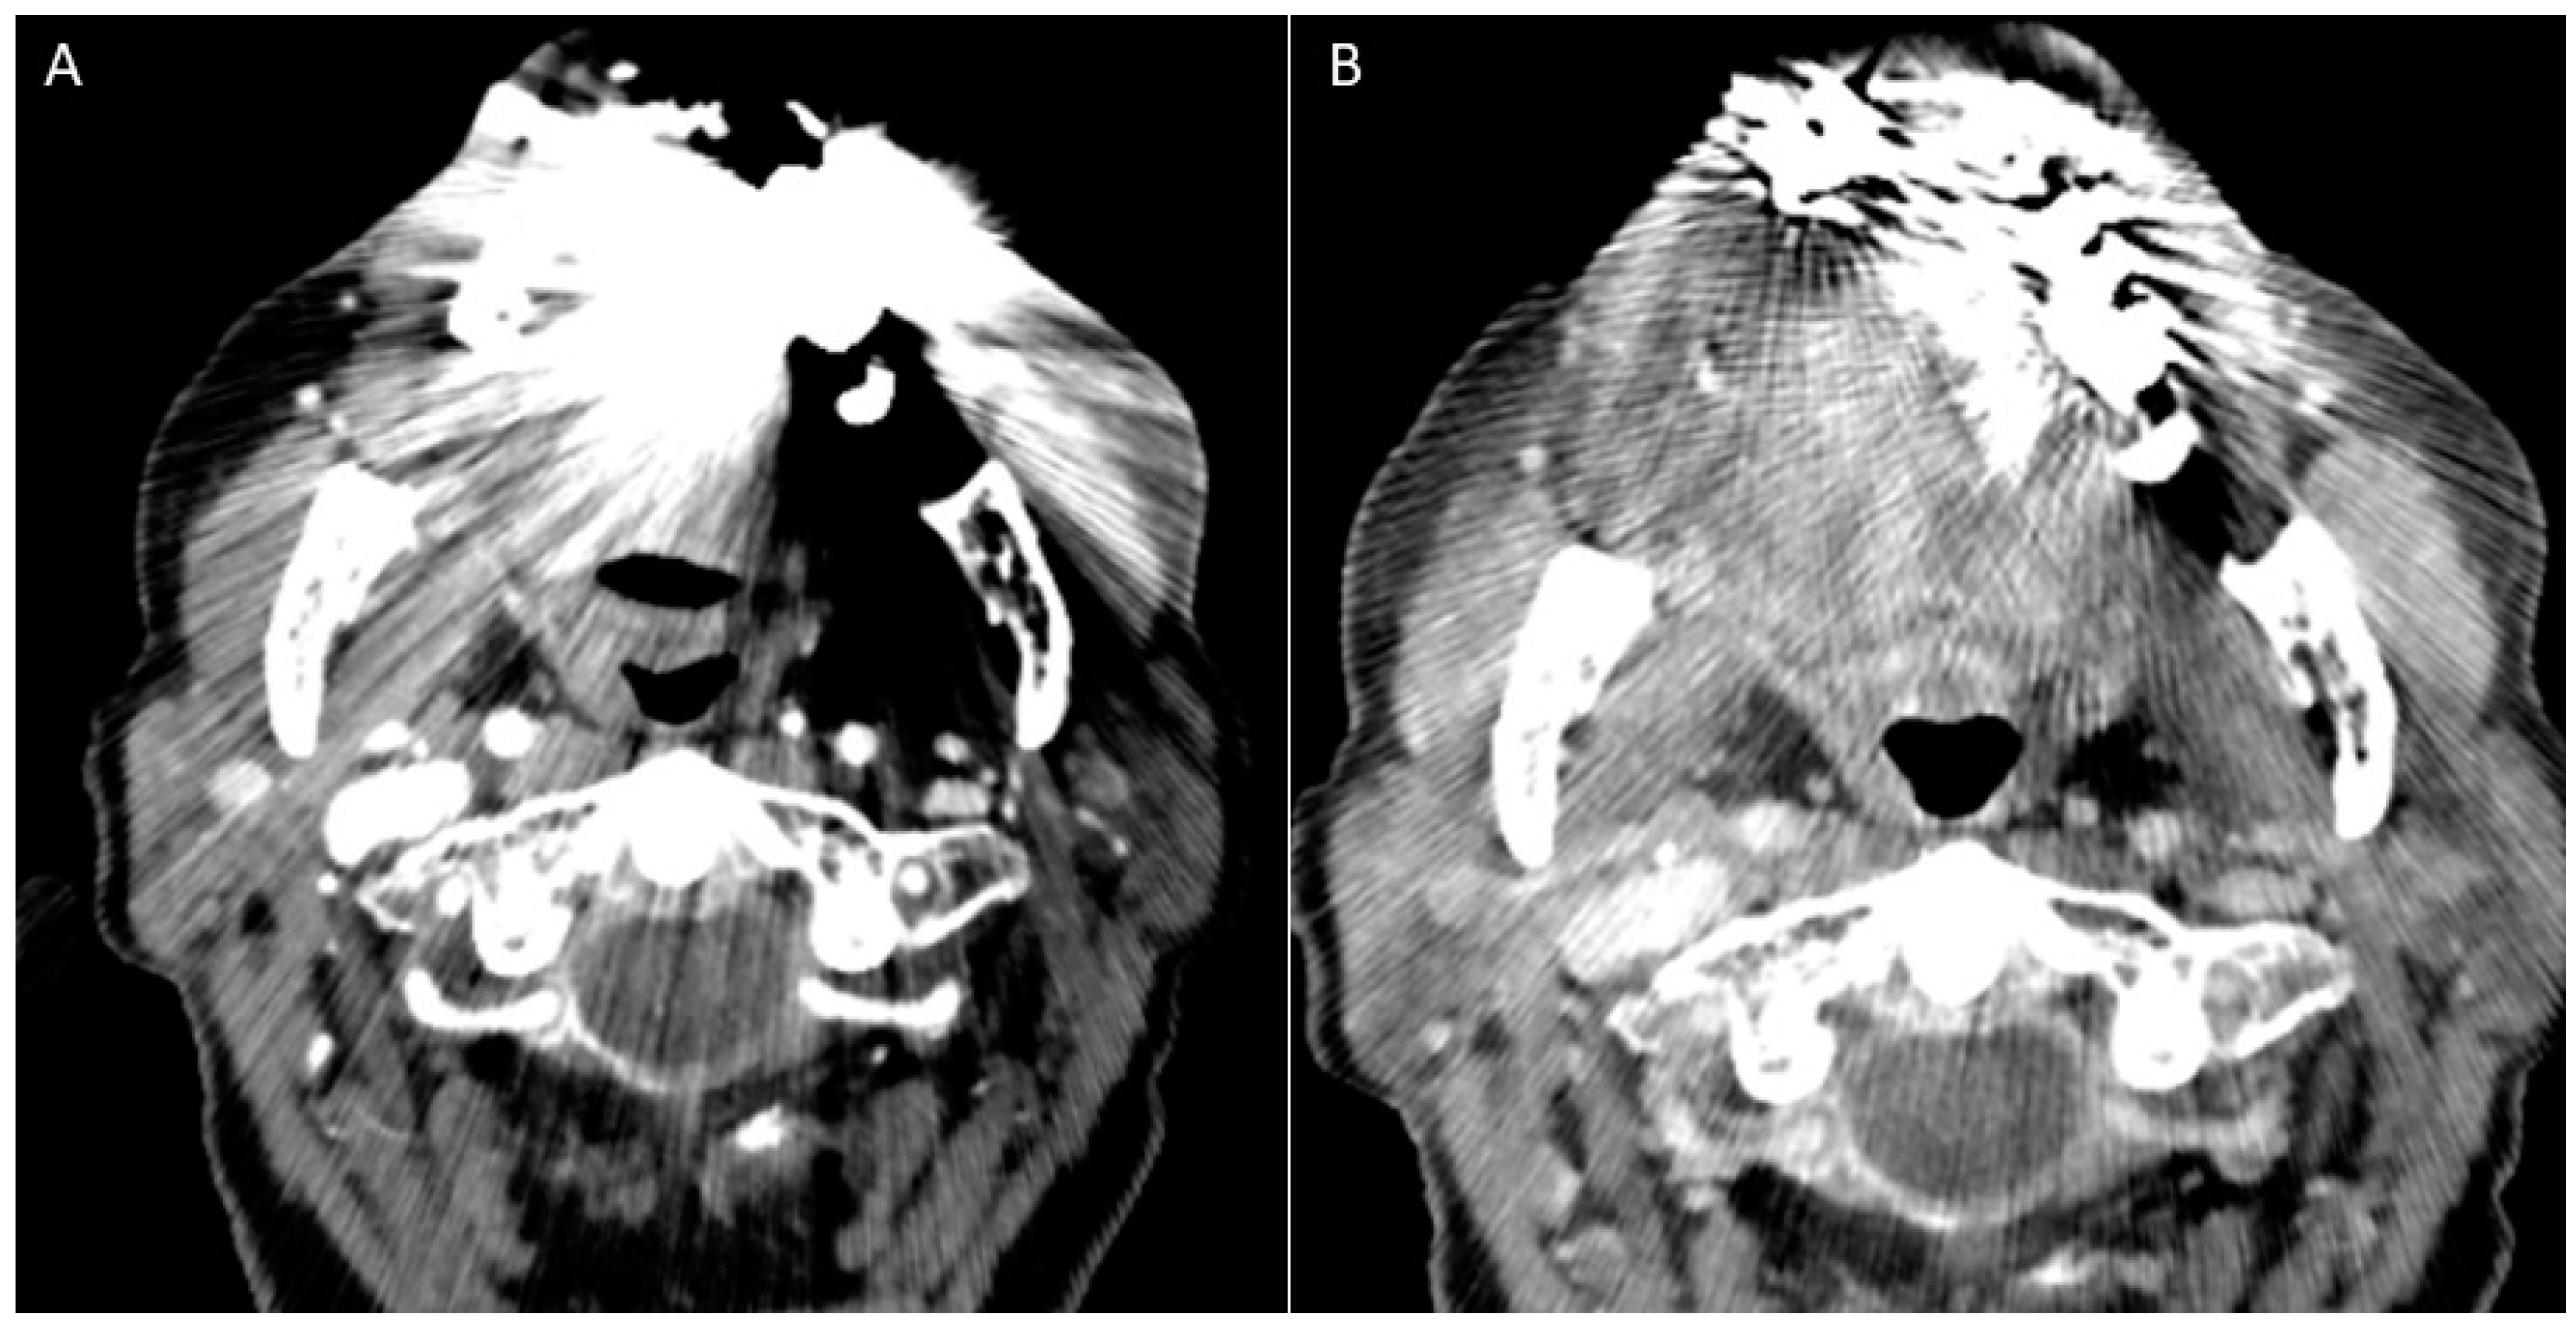

- Puffed cheek technique. The vestibule of the mouth is a virtual cavity due to the contact between the mucosa of the lip, cheek, and gingiva. Puffed cheek technique helps to determine if the lesion is arising from the buccal, gingival, or lingual mucosal surface since patients blow uniformly through pursed lips and the mucosal surfaces appear separated from each other. Therefore, the vestibular cavity can be appreciated as an air-filled horse-shoe-shaped space both on MSCT and MRI (Figure 10 and Figure 11).

- Gantry tilt scanning. Patients have to be positioned with tooth occlusal surfaces perpendicular to the table; the gantry tilt angle used is ≥20 degrees. In the post-processing phase the oblique images obtained are reconstructed to transverse images with information on the table position [53];

- Open mouth dynamic manoeuvre. See the above-mentioned paragraph and Figure 14);